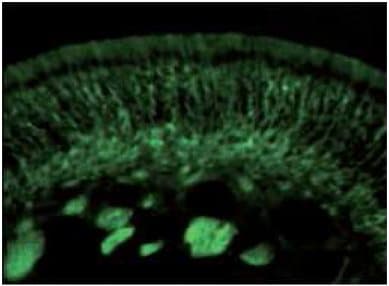

Anti-CRMP5 antibody(ab36203)

Rabbit Polyclonal CRMP5 antibody. Suitable for WB, IHC-P and reacts with Human samples. Cited in 7 publications. Immunogen corresponding to Synthetic Peptide within Human Dihydropyrimidinase-related protein 5.

Applications IHC-P, WB